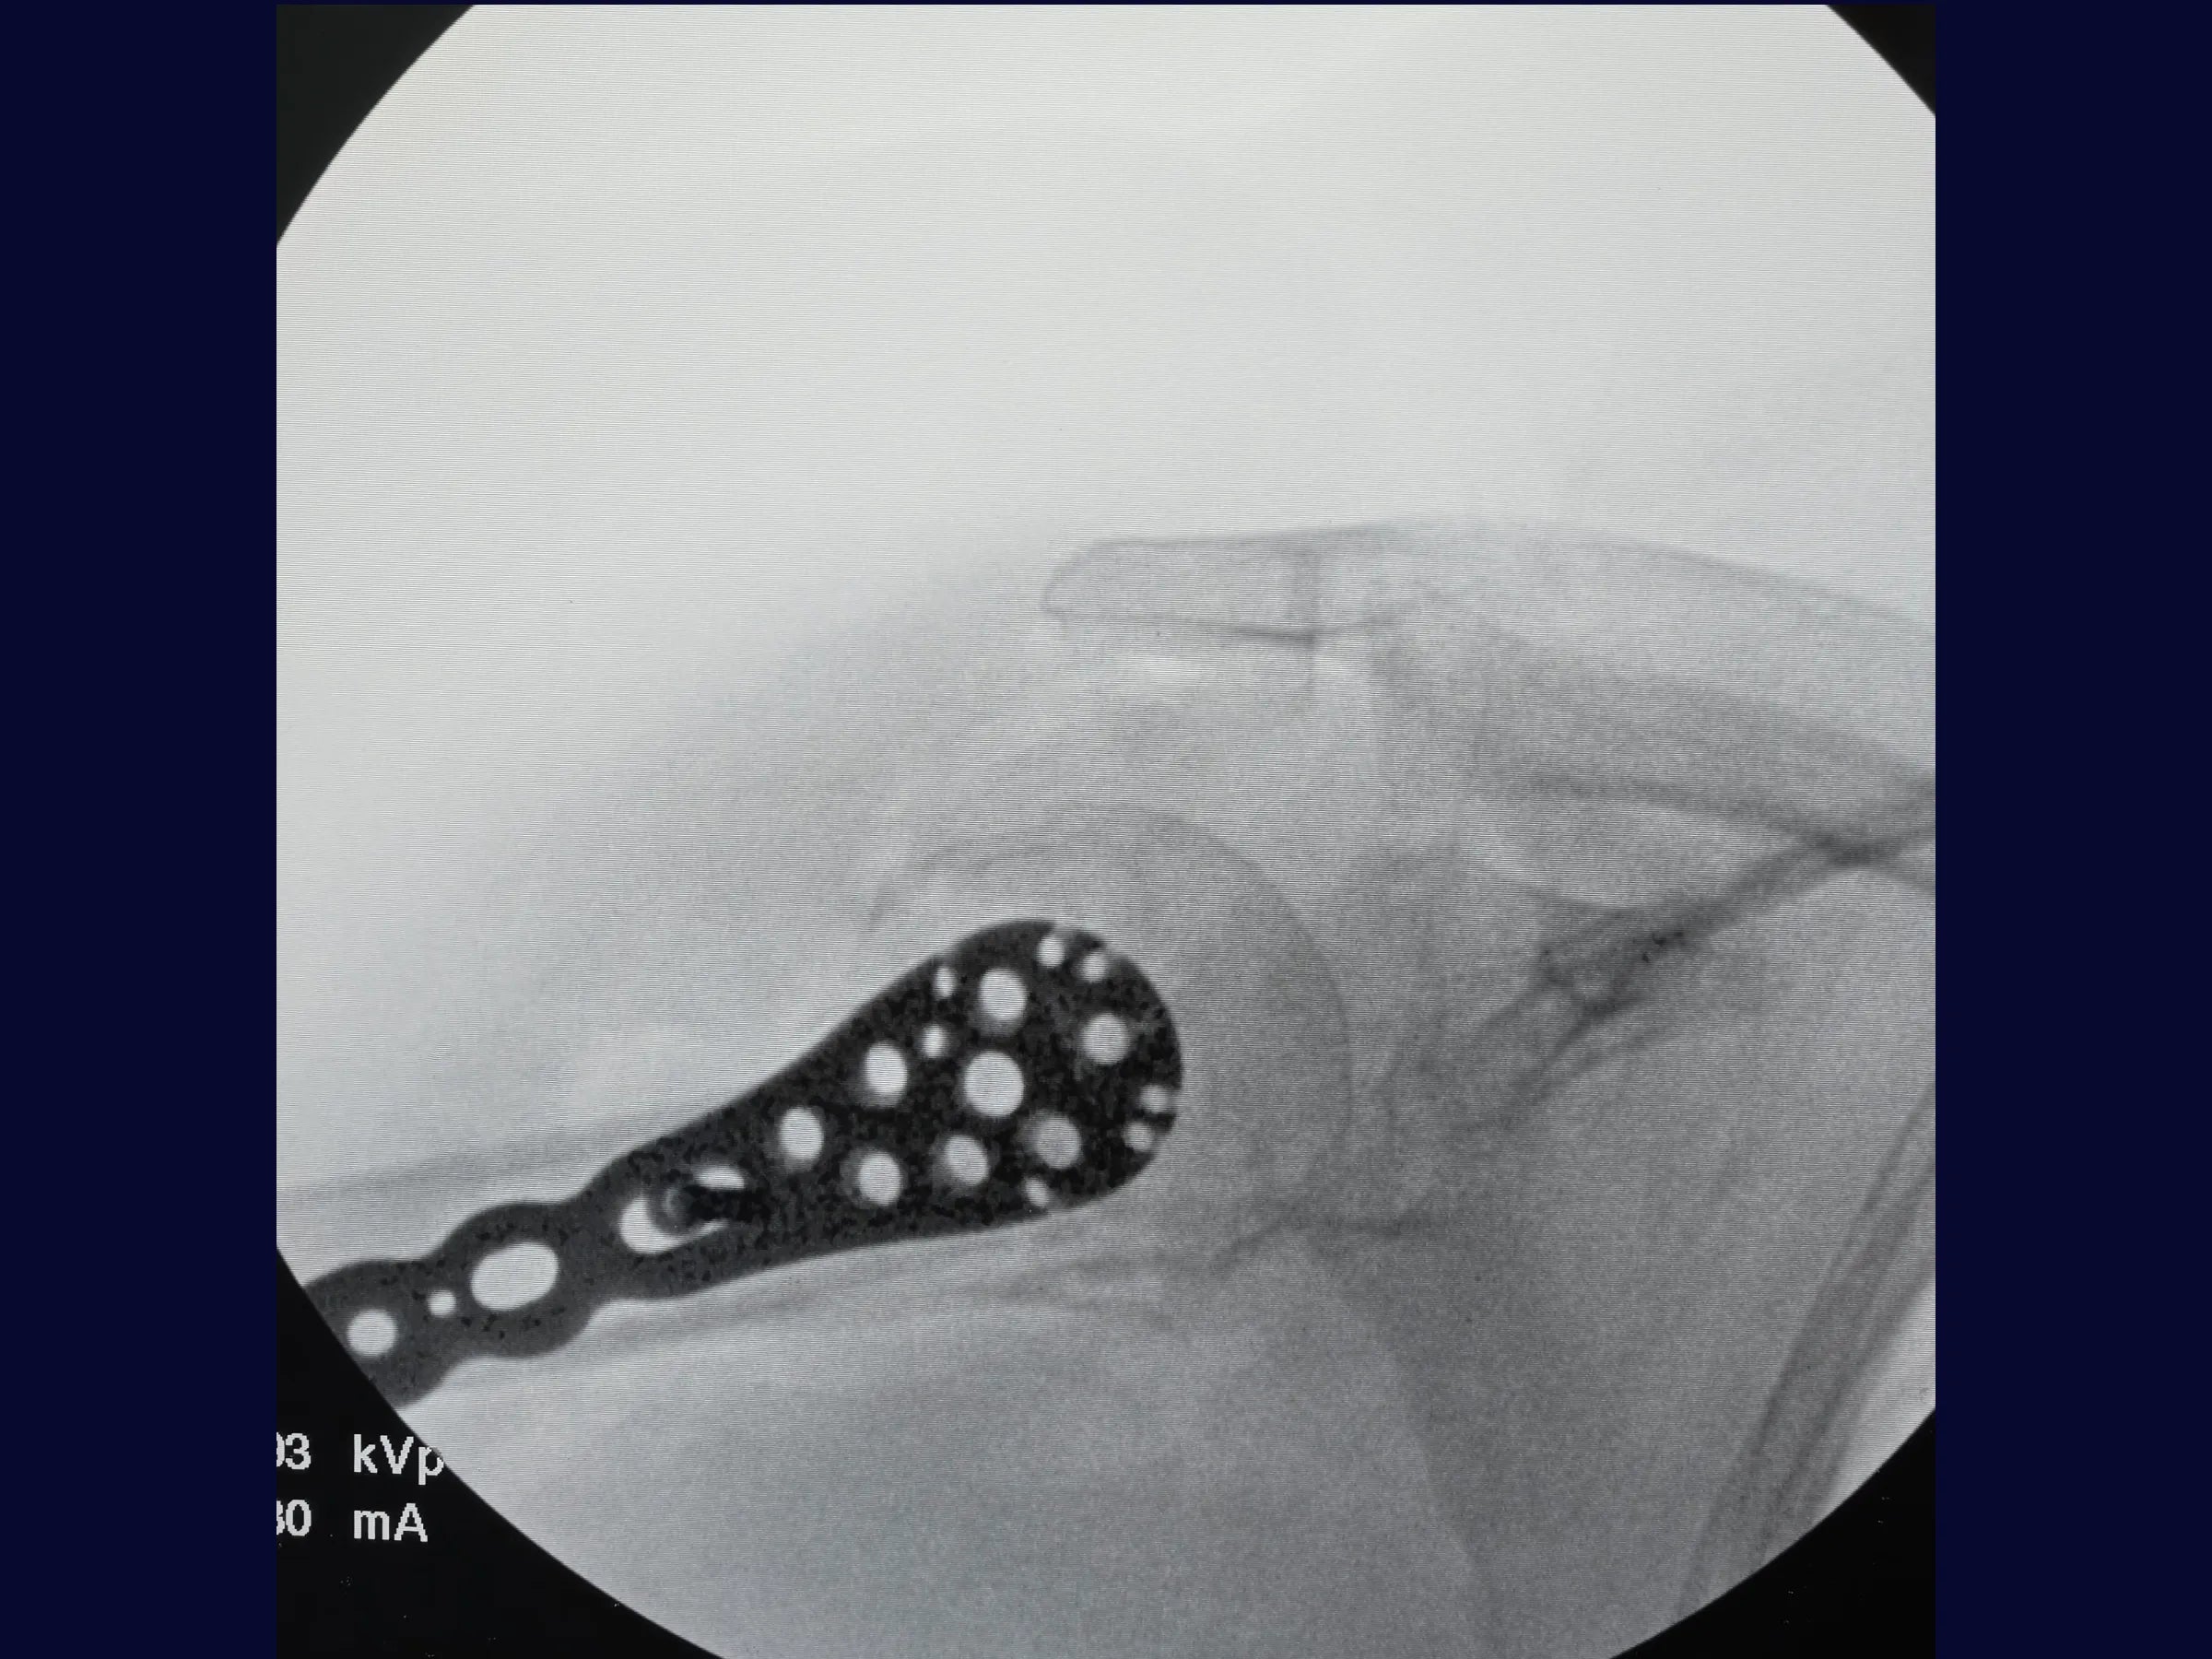

Este treinamento apresenta, passo a passo, a reconstrução do úmero proximal por via deltopeitoral, com ênfase na redução anatômica das tuberosidades e fixação estável com placa bloqueada, demonstrada sob perspectiva cirúrgica detalhada.

- Fixação com placa bloqueada e parafusos do calcar;

- Controle Radiográfico e Ajustes Finais: Correção de cisalhamento e simetria com reposicionamento de parafusos.